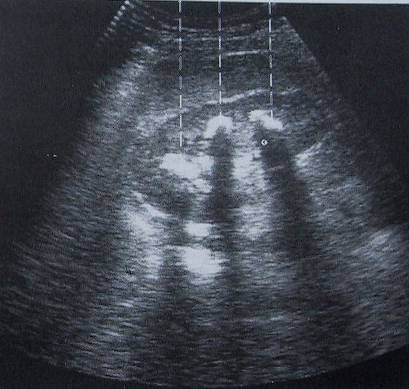

Ultraschalluntersuchungen (Sonographie) ermöglicht die Untersuchung von Organen im Bauchraum (Leber, Gallenblase, Nieren,Bauchschlagader), des Herzens und der Schilddrüse sowie der Halsschlagader. Hierbei können Veränderungen der Organe harmloser(z.B. Cysten) aber auch gefährlicher(z.B. Bauchaortenaneurysma) Art festgestellt werden. Ebenfalls kann hierbei sehr sicher beurteilt werden, ob zum Beispiel Gallensteine oder Nierensteine vorhanden sind. Es handelt sich um ein harmloses und für den Patienten nicht belastendes Untersuchungsverfahren. |